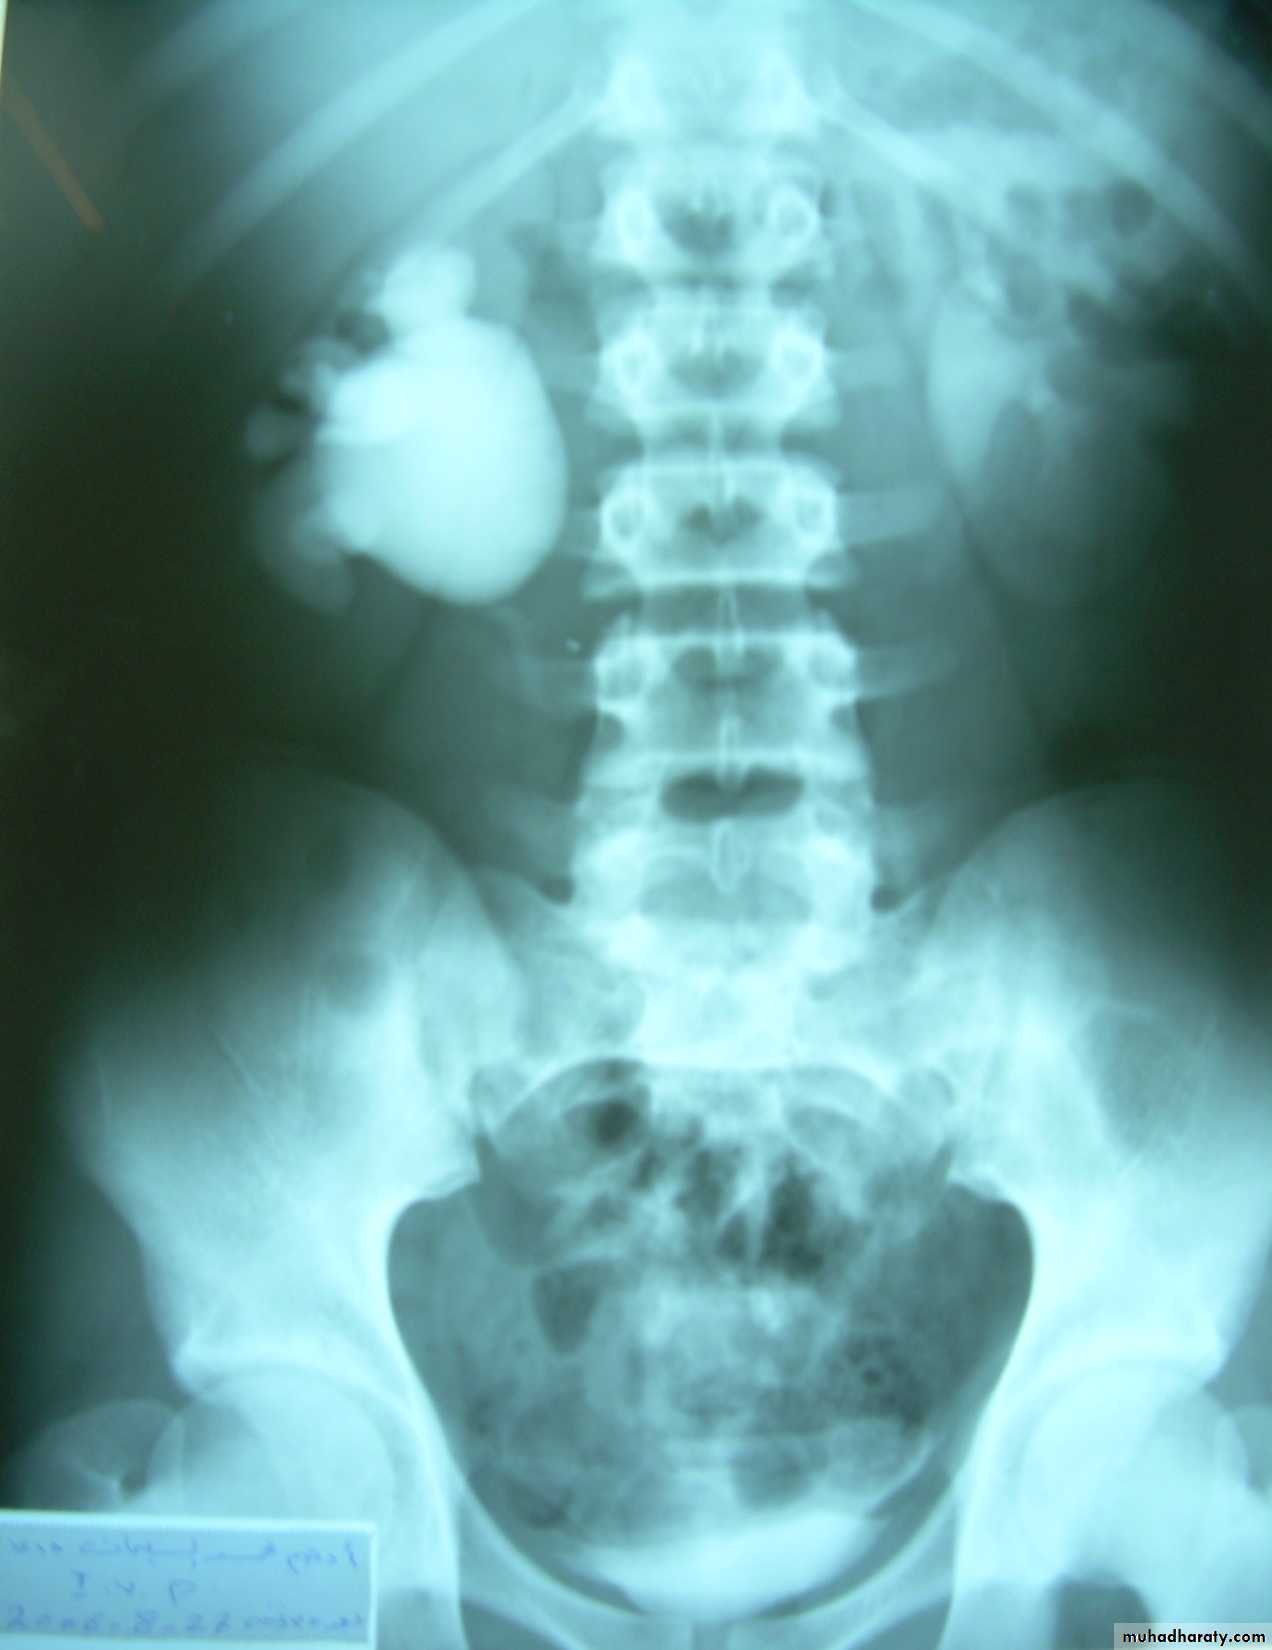

KUB.

Non visualization of the Rt. Kidney either due to early obst. Or type 5 renal injuryWhat's this imaging study?What the abnormal finding?

KUB

Multiple bilateral renal stonesStaghorn stone needs PCNL